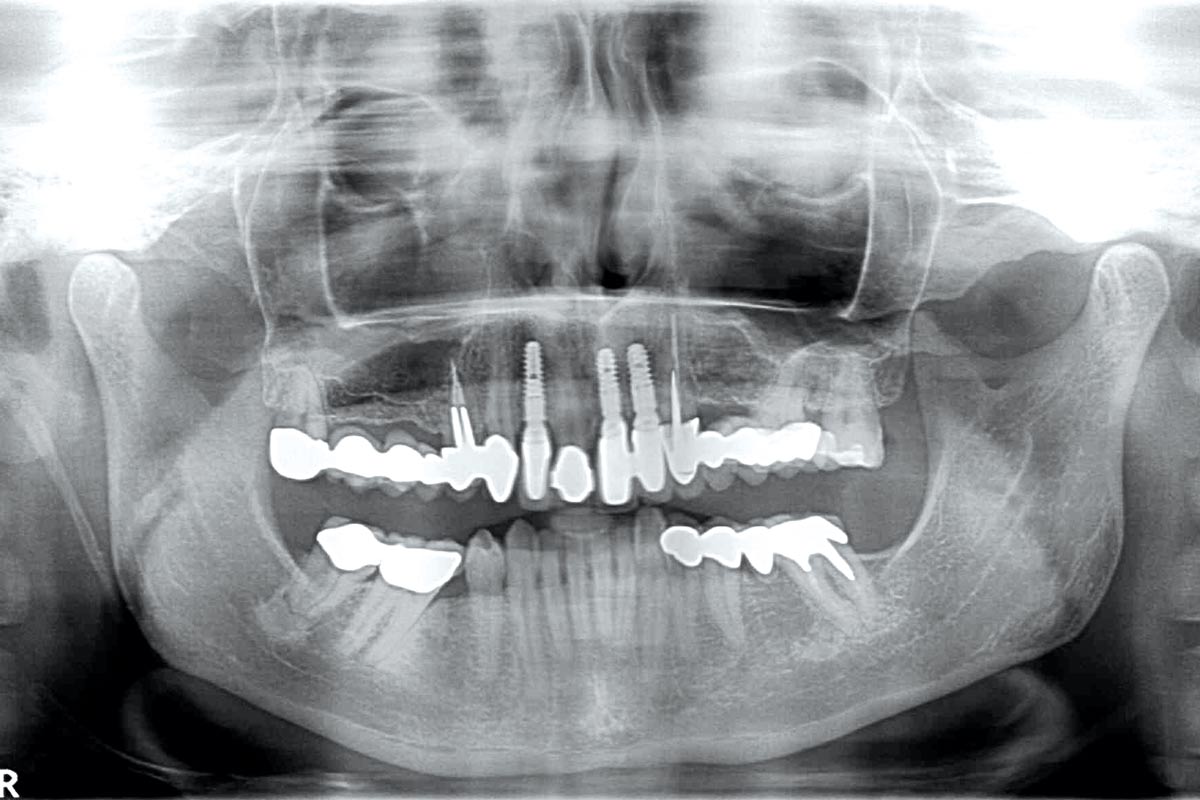

Initial x-ray showing bone loss around implants placed 5 years ago in another dental clinic